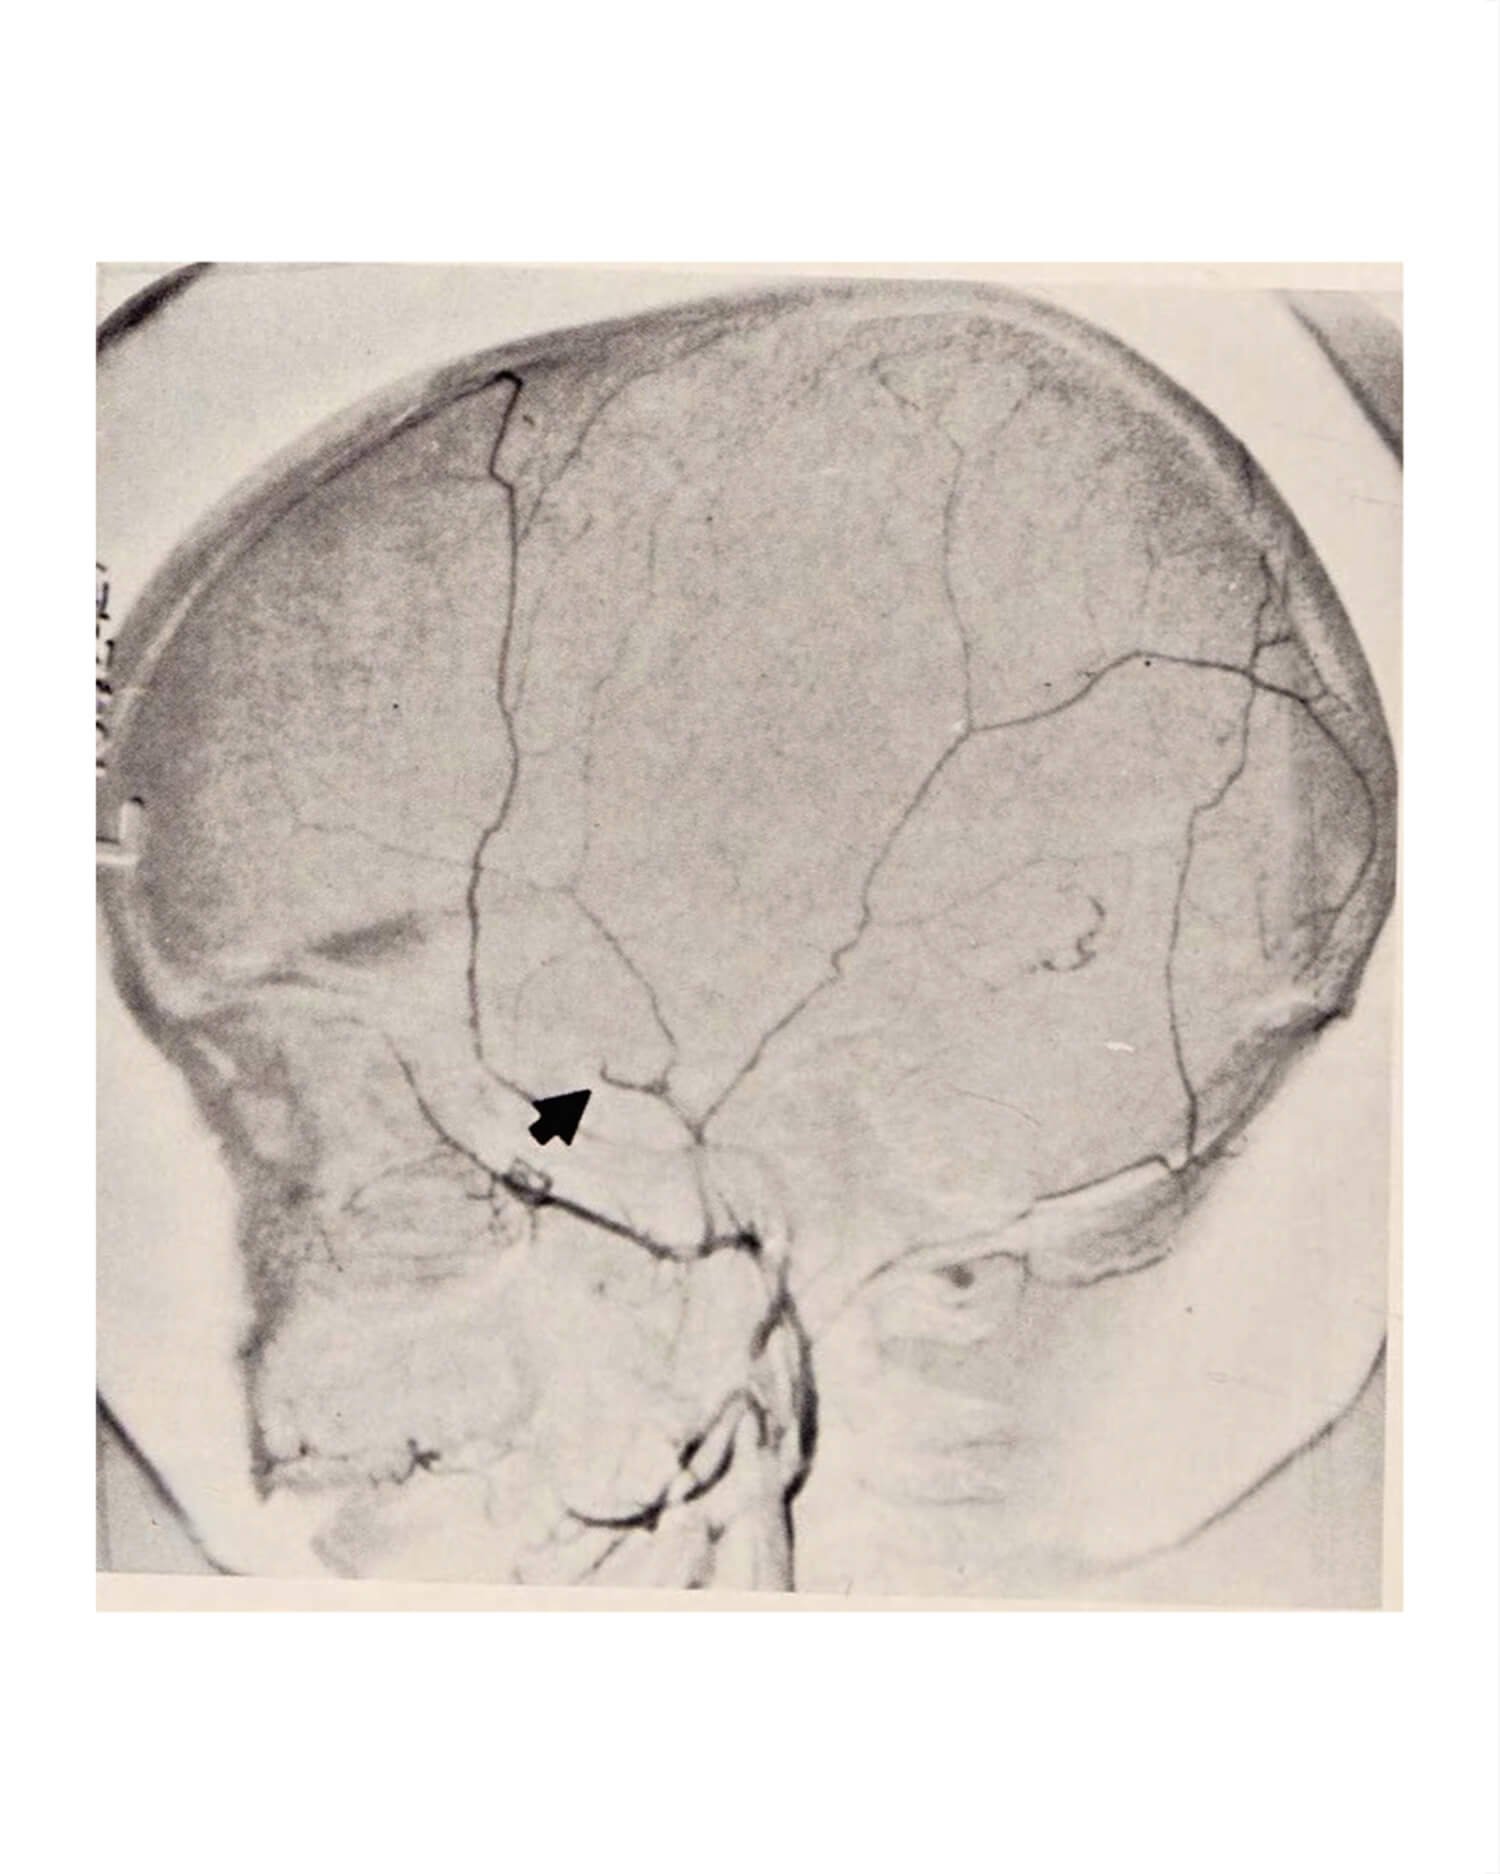

The setting is a small town on the banks of a contaminated river, and the narrative follows how radioactive exposure impacts the human body, society and the wider natural world. Something has clearly happened in the scenes depicted and the accumulating ambiance of the series; the iconography and imagery are clearly recognisable from much modern popular culture. However the rootlessness of time and place allows Nurton to bring his audience on a journey into the possible, the contingent, and as such highlights the ever present, though largely invisible, dangers of radiation and nuclear fallout.

The project’s fictive drive allows Nurton to play with space and time, questioning how such events have unfolded in the past and why they’ve been so prone to secrecy, paranoia and indeed coverup. Though based heavily on research, Nurton presents the story within the frame of a sci-fi script he has developed, making it a dystopian story albeit one wholly honest to real events. By interrogating details, one can parse that everything has a reference – whether it be the date of a disaster, the location of a town, or a man’s bodily injuries. By mining the historical and cultural palimpsests built up around the topic, and adopting a technique of collage, amalgamation and the filmic, Nurton creates a new space that tells the story of this sickness and catastrophe anew.